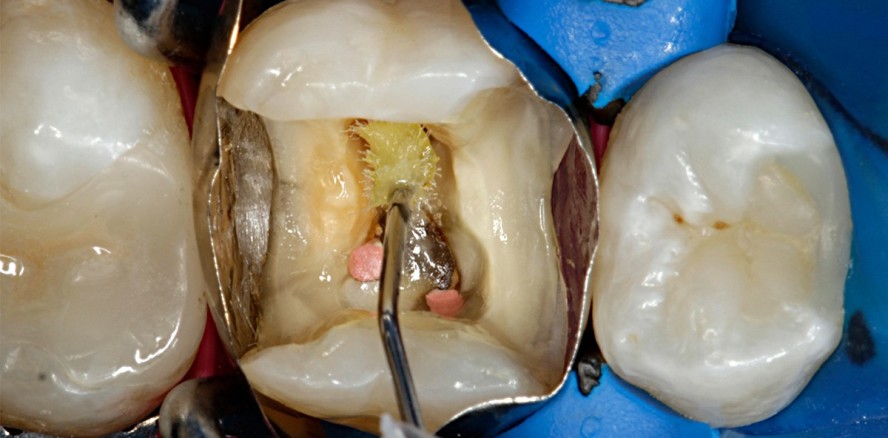

Zudem ermöglicht uns der Einsatz von Adhese Universal ein effizienteres Arbeiten durch weniger Materialien in der Praxis sowie eine einfachere und ökonomischere Lagerhaltung. Außerdem besteht keine Verwechslungsgefahr zwischen verschiedenen Adhäsiven mehr. Die zwei einander gegenübergestellten Fallbeschreibungen zeigen die Verwendung von Adhese Universal für sowohl eine direkte Seitenzahnversorgung wie für eine indirekte Versorgung und unterstreichen damit den dualen Einsatz des Adhäsivs.